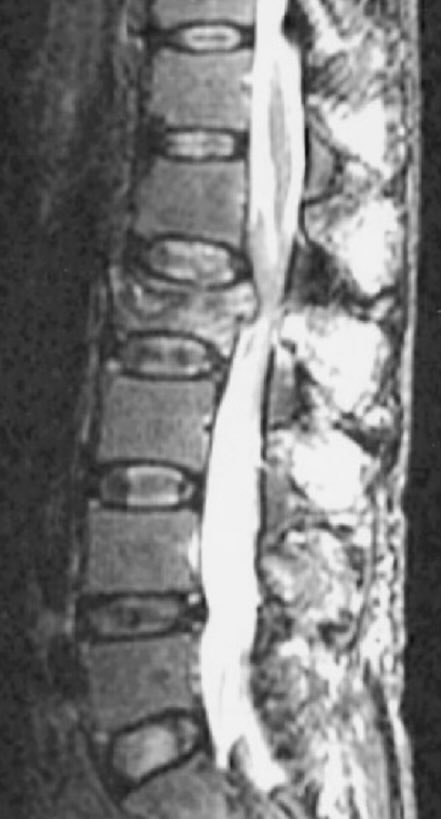

Worsening back pain mostly at night, aged 78, normal ESR and C reactive protein; What is the diagnosis❓